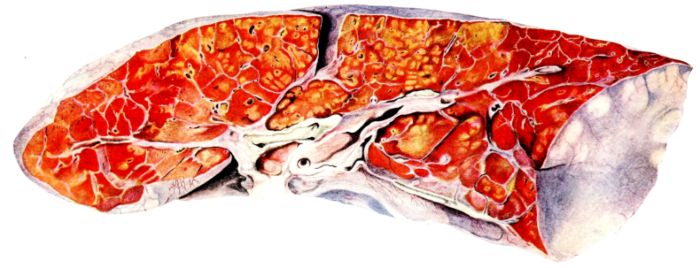

FIG. XIII. AUTOPSY NO. 96. RIGHT LUNG. A WATER COLOR DRAWING OF A GROSS LUNG IN THE ACUTE STAGE. NOTE THE SIZE OF THE LUNG, THE HEMORRHAGES ON THE PLEURAL SURFACE, AND THE BLUE AREAS OF CONSOLIDATION.

FIG. XIV. AUTOPSY NO. 96. LEFT LUNG. NOTE ITS SIZE AND THE PATCHY CONSOLIDATION.

19The lungs are extremely voluminous (12, 17) due in part to an accumulation of liquid within them. This finds its way into the trachea and completely fills the latter structure with blood-stained, syrupy fluid, with purulent material, or with a mixture of these (2, 90, 107, 157, 162). At first the pleural surface is smooth and often quite even, but on closer inspection, a minute granulation is suggested. In many cases even close examination does not allow the conclusion that an exudation of anything but serum has occurred through this membrane, except in localized foci. These foci more frequently involve the interlobar pleura and that of the lower lobes (112, 143). The volume of the lungs, often great enough to obliterate the pericardial area, is one of the two most characteristic features of the external examination. The other feature is their color. Small, bright red hemorrhages may occur anywhere. The larger patches are the most striking. Violet, purple, or dark brown areas, irregular in shape and distribution, are more frequently found on that portion of the pleura over the lower two-thirds of the lung. Between the deeply colored zones, there are pale pink areas which involve the lowermost edge to the least degree, the anterior margin somewhat more, and the apex of the lung most of all. The darker portions just referred to may project above the surface and may be circumscribed, resembling huge, fresh hemorrhagic infarcts (41, 108). The alveolar walls are not seen through the pleural surfaces in these darker zones. The pale pink areas, usually at the level of the more intensely colored zones, may be elevated and the dilated air sacs are distinctly made out through the pleura (Fig. XIII). At the hilum, the lymph glands are large and soft. When cut, fluid escapes and is often blood-stained. The cross section may present a distinct, diffuse, hemorrhagic appearance (162). At the hilus, too, the lymphatics, distended here and there over the surface of the pleura, are most affected. The congested bronchial mucous membrane and the exudate in these structures has been described.

After removal, the lung retains its shape, but is more flaccid than the consolidated lung of lobar pneumonia. It cuts with very little resistance and immediately a large amount of a syrupy, pink fluid escapes and obscures the entire area. With the fluid scraped away, the variations in the consistency of the lung become visible. The pale areas around the borders and chiefly at the apex in which the air sacs are discernible with the naked eye, sink slightly below the remainder of the surface, and the pleural edge inverts. The individual lobules of the lung in these areas are more conspicuous than normal, because the interstitial tissue bearing the lymphatics and vessels, as well as that around the bronchi and larger blood vessels, does not lose its edematous appearance as quickly as the alveoli (40, 92, 110, 164), and, consequently, these grey lines and points stand up somewhat more prominently.[6] In contrast with the paler areas which are prone to slight collapse, the remainder of the cross section retains its more smooth and even surface. The alveolar walls are not distinctly made out, but the terminal bronchioles often make themselves evident by the nature of the material which is within and by their distinct dilatation (1, 67, 110, 149, 162). The more firm areas stand out, too, on account of their difference in color. The scheme is not unlike that seen on the pleural surface, and while dark, almost black, infarct-like areas occur on the cut surface, the solid areas are more likely to be translucent, dull, light red, brown or even grey. They have a surface similar to a very fresh, tuberculous, gelatinous pneumonia, but the color differs from the cloudy grey of the latter on account of the admixture of blood in the exudate and the great congestion of the vessels (Fig. XIV).

The well developed post-mortem muscular rigidity, the lividity of the dependent parts, of the face with its mucous membranes, and often of the trunk, the jaundice variable in extent, the crusts of blood on the nares and mouth, and the splanchnic dilatation are features which prepare for the gross picture presented by the thoracic organs. The increased moisture within the pleural cavities associated with the even, translucent pleural surface, whose dilated lymphatics become more and more prominent towards the hilum, the large succulent lymph glands, and the exudate in the bronchial tree, are all striking, but more characteristic of the gross picture, is the great increase in volume of the lung itself, mottled 20with brilliant colors. The lung, too, is very wet and on section, after the syrupy, blood-stained fluid escapes from the less definitely consolidated zones, the latter appear, not as the usual granular, firm areas of hepatization, but have more the consistency of a gel, and also its translucence. Characteristic of this disease as these changes may be, the specificity of the fundamental lesion in the respiratory tract, becomes more emphatic after study of its histology (92, 162).